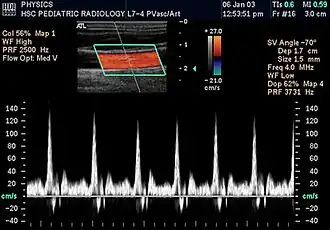

Colour Doppler shows the direction of the blood flow in red or blue (either towards or away from the transducer). Meanwhile, spectral Doppler not only shows the direction of blood flow, it also shows the phases (pulsatility) and acceleration of the blood flow. Any sudden changes in direction of blood flow produces audible sounds on the ultrasound machine.[3]

In spectral Doppler, the y-axis shows the direction and velocity of the flow. Meanwhile, the x-axis (as known as "baseline") shows the flow over time. The gradient at any point on the waveform would therefore shows the acceleration of the flow. In "antegrade" flow, the blood flows according to the normal flow within the circulatory system (e.g. veins flow towards the heart while arteries flows away from the heart). In "retrograde" flow, the flow would reverse (e.g. veins flow away from heart or arteries flow towards the heart). However, "retrograde" flow can be both abnormal or normal. For example, in portal hypertension, there is an abnormal portal venous flow where it flows away from the liver (hepatofugal flow) instead of the normal flow towards liver (hepatopetal flow). In jugular venous pressure waveform of the internal jugular vein, the retrograde "a" waveform is a normal flow due to right atrium contraction. Both antegrade or retrograde flow can be either towards or away from the probe transducer, depending on the position of the probe relative to the blood flow. Blood flow toward the transducer would appear above the baseline while blood flows away from the transducer will appear below the baseline. Waveform of the flow can be classified as: pulsatile (as in arteries), phasic (as in veins), non-phasic (as in diseased veins), and aphasic (no flow). Spectral broadening (thickness of the waveform) increases from large vessels (plug flow) to medium vessels (laminar flow) to small/stenotic/diseased vessels (turbulent flow) due to a larger variety of blood with different ranges of velocities in those with turbulent flow.[3]